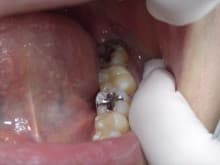

左下奥歯の治療をご紹介します。

銀歯が入っていた歯で

2次虫歯(虫歯のの再発)になっていました。

虫歯を顕微鏡(マイクロスコープ)を使って除去し

再発の少ない

ハイブリットセラミックによる

ダイレクトボンディング治療で行いました。

治療途中です。